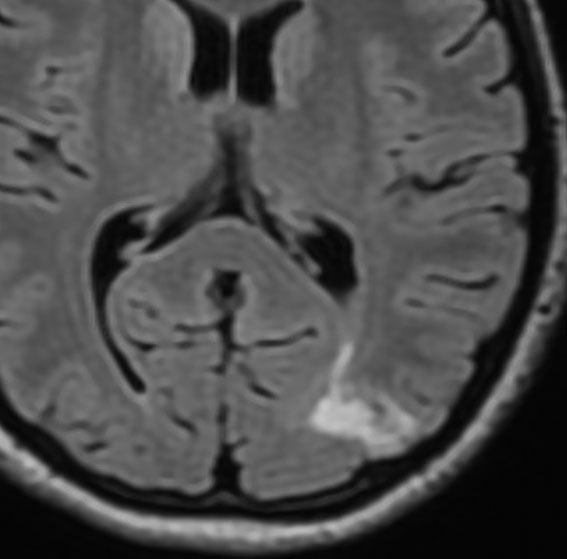

限局性のびまん性星細胞腫

無症状で発見された若年成人のびまん性星細胞腫,一つの脳回に限局するタイプでsingle gyrus gliomaといいます